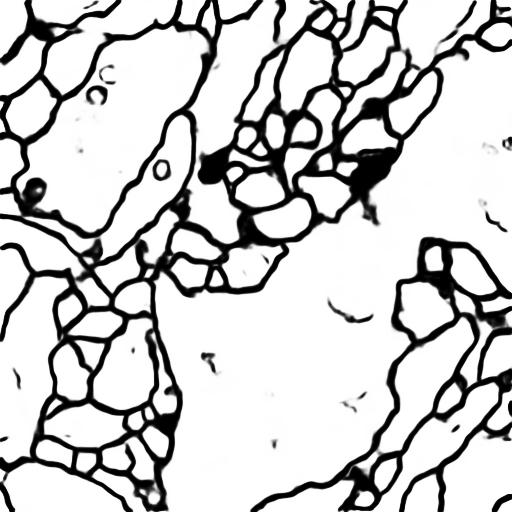

The images are 3-D volume tiff, you should transfer the stacks into images first. The data for training contains 30 512*512 images, which are far not enough to feed a deep learning neural network. To do data augumentation, an image deformation method was used, which was implemented in C++ using opencv.

Output from the network is a 512*512 which represents mask that should be learned. Sigmoid activation function makes sure that mask pixels are in [0, 1] range.

After this script finishes, in imgs_mask_test.npy masks for corresponding images in imgs_test.npy

should be generated. I suggest you examine these masks for getting further insight of your model's performance.

Use the trained model to do segmentation on test images, the result is statisfactory.